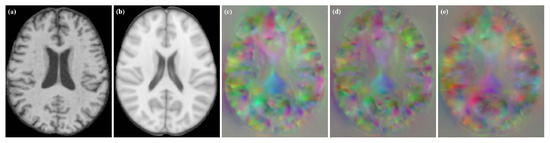

To verify the robustness of the method, we tested it on VoxelMorph and Label-reg models. The experimental results are shown in Figure 9. We found that we obtained DDF without grid-like artifacts under different models.

Figure 9.

Moving image, fixed image and DDFs obtained for different models. (a) moving image; (b) fixed image; (c) VoxelMorph; (d) VoxelMorph (JD); (e) Label-reg.